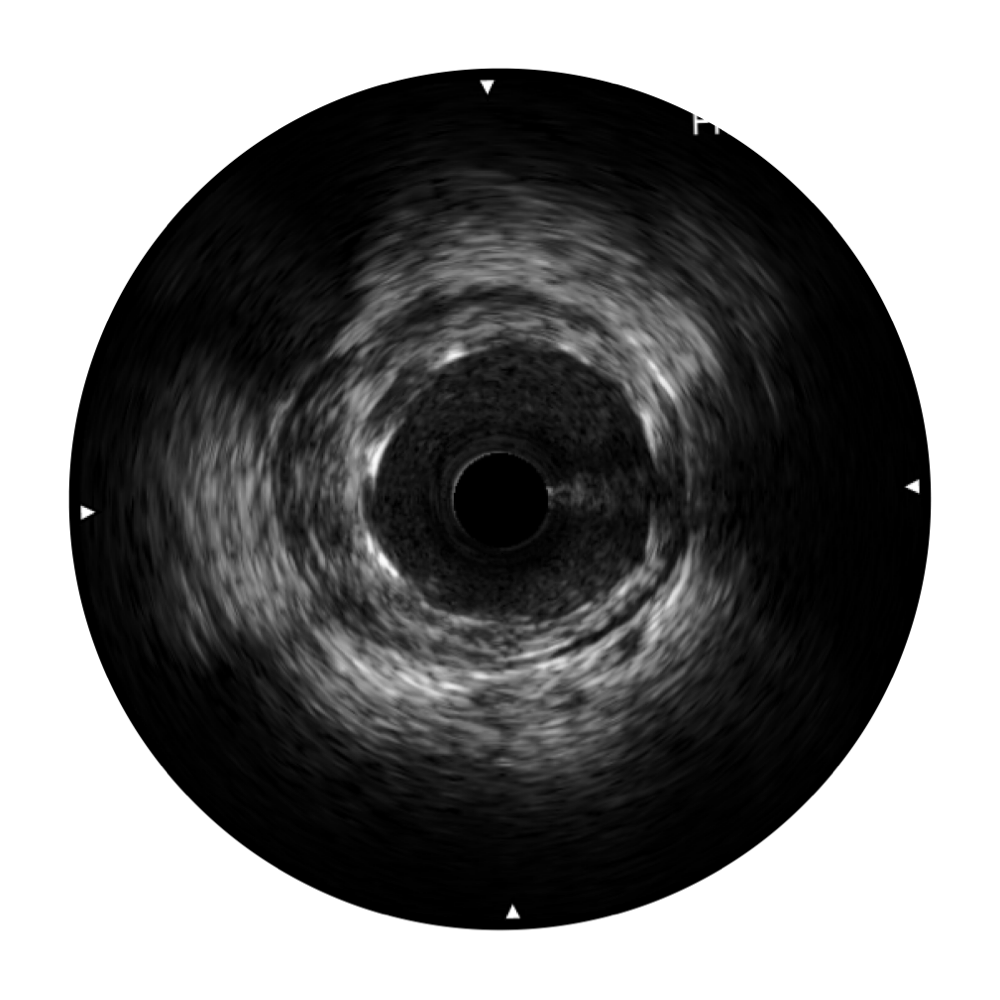

传统IVUS图像

对比传统IVUS导管成像,milan米兰宽频IVUS图像的近场支架梁显影更细腻,远场中膜外血管仍清晰可辨,兼顾远中近,兼顾分辨力与穿透深度